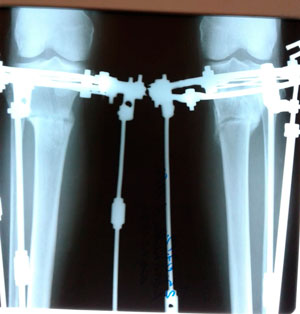

Дата операции - 08.04.2019г.

Дата снятия аппаратов - 25.07.2019г.

Срок сращения - 105 дней.